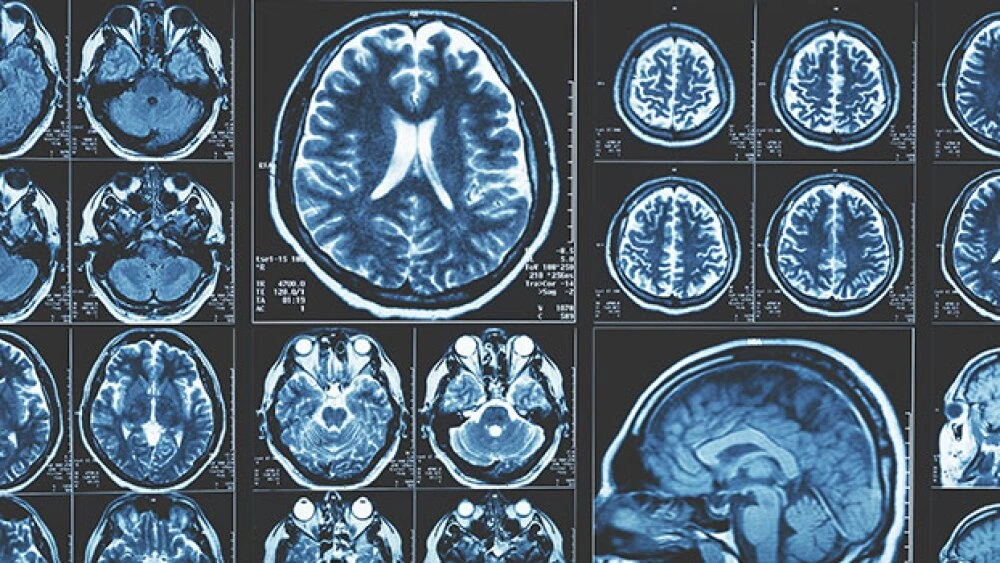

Publié dans la revue Brain Research, l’étude s’est concentrée sur l’hippocampe, la zone du cerveau responsable de la mémoire et de l’apprentissage. Les chercheurs ont mesuré l’impact des exercices aérobiques sur des indicateurs clés de la maladie d’Alzheimer, tels que les plaques amyloïdes (amas de fragments de protéines appelés bêta-amyloïdes) et les enchevêtrements de protéines tau (principal composant des enchevêtrements neurofibrillaires dans les cellules), ainsi que l’accumulation de fer dans les cellules productrices de myéline.